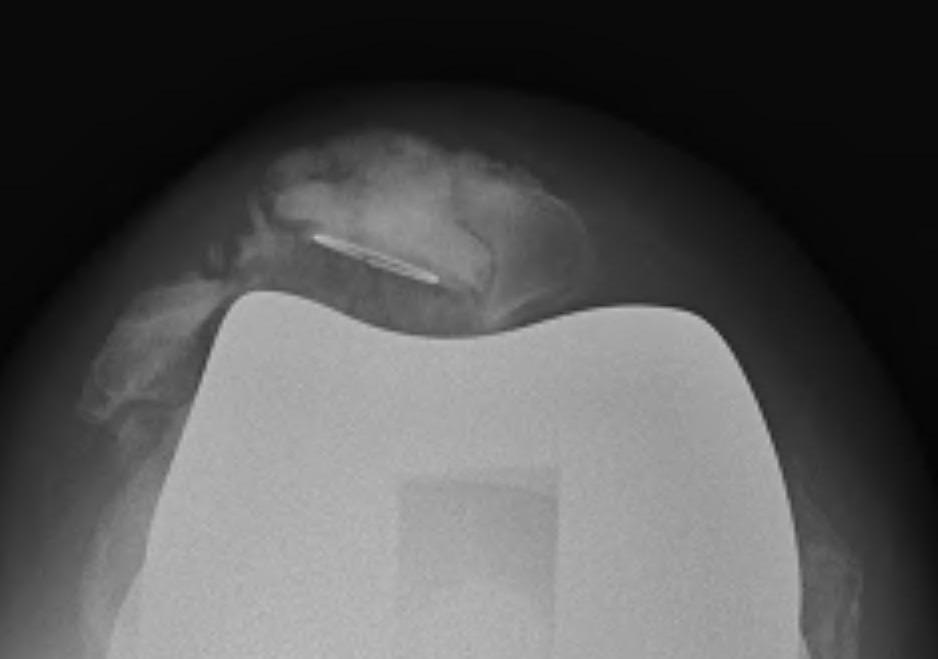

Surgical options

1. Lateral release + Patella resurfacing

2. Tibial tuberosity transfer +/- MPFL reconstruction

![]()

Barber et al Arthroscopy 2008

- 91% successul in eliminating instability in 35 knees

- used Elmslie Trillat